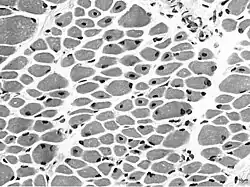

Typische Histologie mit zentralisierten Kernen.

In der Muskelbiopsie sind bei allen Formen unreife Muskelfasern mit einer hohen Zahl zentraler Kerne auffällig, deren histologisches Bild an das fetale myotubuläre Entwicklungsstadium der Skelettmuskulatur erinnert. Es dominiert eine Typ-1-Muskelfaseratrophie.[5]